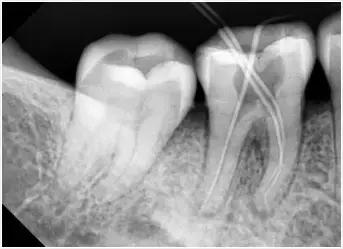

1、术前拍摄X线片

在根管治疗过程中,在根管治疗术前拍X线片,以帮助诊断,了解髓室的位置和根管数目及形态,测量根管工作长度及日后随访和评价疗效提供对比的依据。

3、确定根管工作长度

应用平行投照X线方法、根管长度测量仪确定根管度,最好插针拍X片。